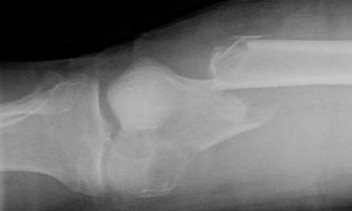

A 28-year-old rugby player presents unable to actively flex the distal interphalangeal (DIP) joint of his ring finger after grabbing an opponent's jersey. Radiographs reveal a small bony avulsion fragment located at the level of the proximal interphalangeal (PIP) joint. According to the Leddy and Packer classification, what type of injury is this?

Explanation

Jersey finger represents an avulsion of the flexor digitorum profundus (FDP) tendon. Leddy and Packer classification: Type I involves retraction to the palm, both vincula ruptured (high risk of ischemia, requires urgent repair). Type II involves retraction to the PIP joint level, where it is held by the intact vinculum longus; a small bony fragment may be seen at this level. Type III involves a large bony avulsion that is caught at the A4 pulley (DIP joint level). This patient has a Type II injury.